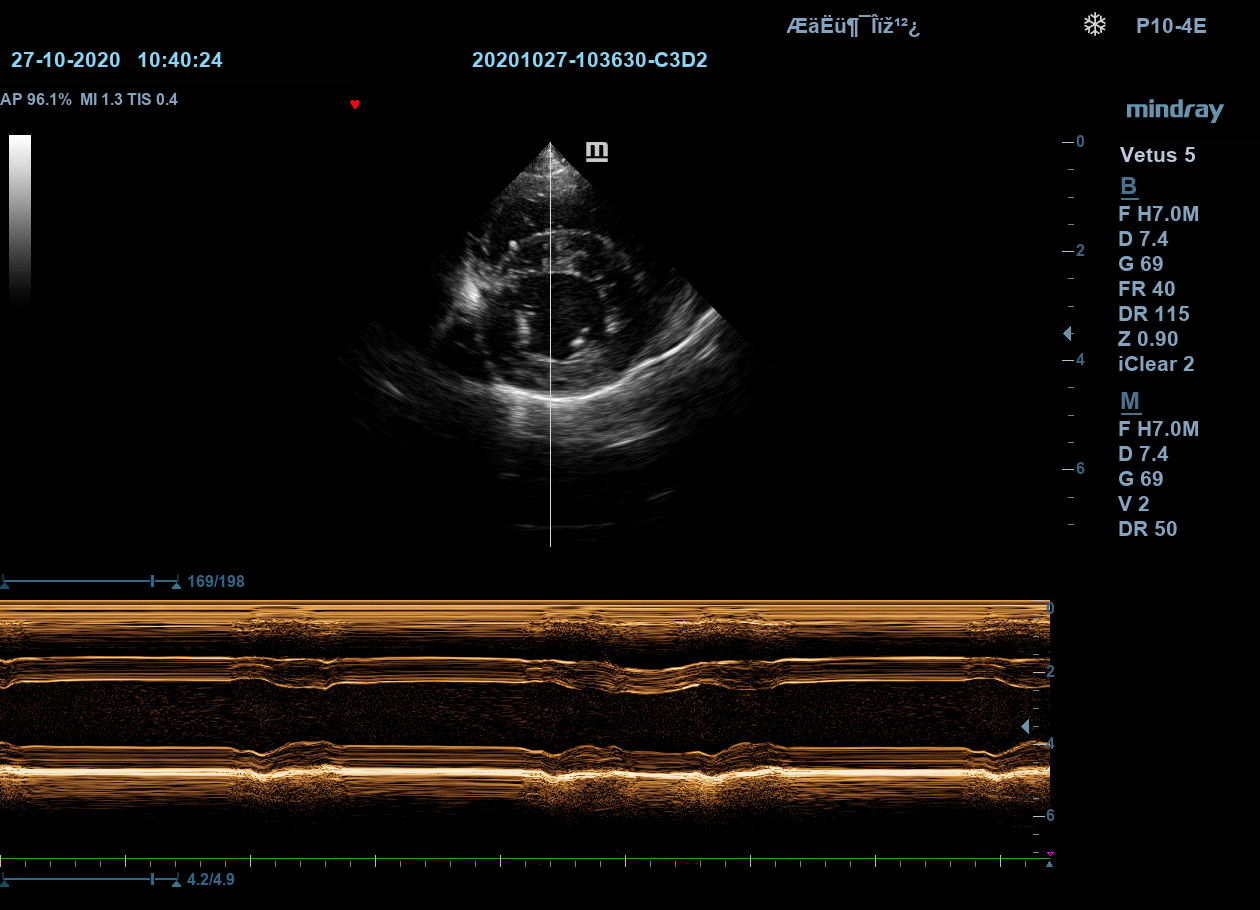

Free Xros M – анатомический М-режим

При наличии записанной в память прибора видео петли, режим позволяет провести линию М-режима в любом месте, при этом корректируя изначально не оптимальный угол.

Free Xros M – анатомический М-режим

При наличии записанной в память прибора видео петли, режим позволяет провести линию М-режима в любом месте, при этом корректируя изначально не оптимальный угол.